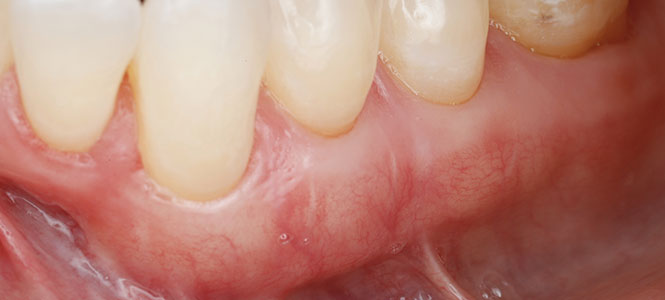

A healthy smile depends on strong, protective gums. But when gum tissue begins to recede, the roots of your teeth are left exposed. This can cause sensitivity, make your teeth appear longer, and increase your risk of decay and tooth loss. For many people, gum recession happens so gradually that they don’t notice until discomfort—or even damage—appears.

Gum Grafting

Transplanting healthy tissue to areas where the gums have receded, covering exposed roots and creating a stronger protective barrier.

What You Can Expect from Treatment

Our goal is to make the process comfortable and predictable. During your visit, we’ll explain your treatment options clearly and ensure you understand the benefits of each. Modern periodontal techniques allow for less discomfort, faster recovery, and long-lasting results.